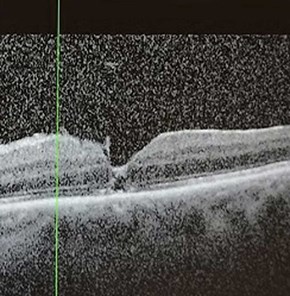

During the second postoperative week, the gas bubble had diminished to just over half of the patient’s visual field. The patient reported that routine activities requiring binocular vision, such as reading and watching television, became increasingly disorientating and difficult to manage. Their vision whilst reading and looking down has been illustrated in Figures 6 and 7. At their follow-up review, the OCT confirmed anatomical resolution of the macular hole, as demonstrated in Figure 8.

Figure 8: Macula OCT 2 weeks postoperatively [3].